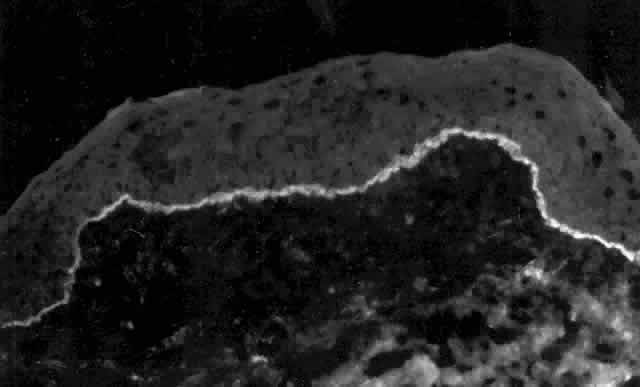

Pemphigus (from the Greek meaning puff or blister) comprises a group of autoimmune vesiculobullous eruptions of the skin and mucous membranes that are seen primarily in middle-aged people, with both sexes being affected equally.3 Involvement of mucosae may occur as the initial manifestation in as many as 25% of cases, and it occurs at some point during the course of disease in 95% of cases.4 Pemphigus vulgaris and its variant, pemphigus vegetans, constitute a more acute form of the disease in which the earliest lesions appear in the oral mucosa and are then followed by a bullous eruption of the skin over the trunk and extremities within 4 to 12 months (Fig. 1). This form of pemphigus was almost uniformly fatal prior to the use of systemic corticosteroid therapy. The mortality rate was reduced to approximately 40% by the use of steroids and has been further reduced to 5% by the addition of immunosuppressive chemotherapeutic regimens for the most difficult cases. Pemphigus foliaceus and its variant, pemphigus erythematosus, follow a more chronic but benign course. Mucosal lesions are unusual in this form, which is primarily an exfoliative dermatitis.3

Pemphigus can be differentiated from bullous pemphigoid and from cicatricial pemphigoid on histologic and immunologic bases. Whereas the bullae in pemphigus are intraepidermal, those occurring in bullous pemphigoid and in cicatricial pemphigoid are subepidermal, between epidermis and dermis, or between mucosa and submucosa. Acantholysis is not present in the latter two conditions.5 In bullous pemphigoid and in cicatricial pemphigoid there are tissue-fixed immunoglobulins in the subepidermal basement membrane zone (Fig. 2).11 This is in contrast to the interepidermal fixation of antibodies (Fig. 3) seen in pemphigus (Table 1).